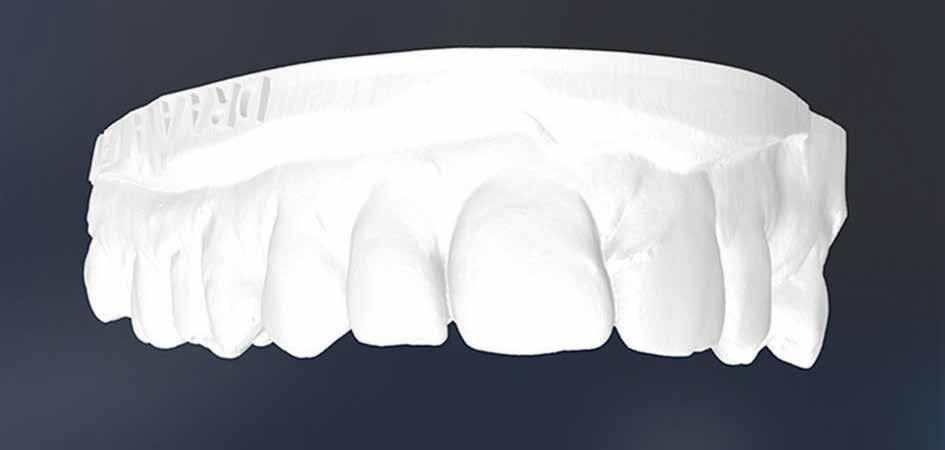

A felnőtt páciensek kezelése során általában egyszerre több ellátásra szoruló elváltozást is diagnosztizálhatunk: hiányzó fogak, kopott fogazat, esetleg régi, nem megfelelő, sérült fogpótlások, rendellenes helyzetben lévő fogak stb… Ezen páciensek kezelésekkel kapcsolatos kérései mindig az esztétikai vagy a rágással kapcsolatos kívánságaik kielégítését szolgálja. A kezelések során a fogorvosoknak nem csak a páciensek kéréseinek teljesítésére, hanem ezzel egyidejűleg a fogazat általános megjelenésének és funkciójának lehetőség szerinti javítására is törekedniük kell. Mindemellett a lehető legtöbb saját foganyag megőrzését és az évek során elvesztett kemény- és lágyrészek pótlását (pl.: hiányzó fogak, sorvadt állcsontgerinc, lágyszöveti defektusok) is szem előtt kell tartaniuk, úgy, hogy közben egy hosszú távon fenntartható eredményekkel járó kezelési tervet állítanak össze. Ezek mindig összetett esetek. Annak érdekében, hogy a fentiekben megfogalmazott összes kezelési célt teljesíteni tudjuk, interdiszciplináris megközelítésre van szükség. Az ilyen komplex rehabilitációs kezeléseket „fogászati megfiatalításnak” nevezzük. Ezeknek a beavatkozásoknak lényege az elhasználódott fogazat biológiai szempontokat figyelembe vevő minimál invazív módon történő helyreállításában rejlik, mely folyamat végére a páciensek fogai visszanyerhetik fiatalkori megjelenésüket.

A rehabilitációs kezeléseknek a célja, hogy a páciensek a lehető leghosszabb időn keresztül képesek legyenek mosolyogni és rágni. A protetikai kezeléseket végző fogorvosoknak helyre kell tudni állítaniuk a fogívek szabályos lefutását és az alsó és felső fogív között megfelelő interokkluzális érintkezéseket kell létrehozniuk. Így lehet csak az ellátás befejezését követően elért végeredmény biológiai szempontokat figyelembe vevő esztétikáját, funkcionális megfelelőségét, hosszú távú fenntarthatóságát biztosítani.

A preprotetikai fázisban el kell látnunk a diagnosztizálásra került kórfolyamatokat, megfelelő pozícióba kell állítanunk a megtartani kívánt fogakat, pótolnunk kell az elvesztett csontállományt, valamint gondoskodnunk kell az íny megfelelő állapotáról. Ha szükség van rá, úgy a foghiányok pótlására szolgáló dentális implantátumok is ebben a fázisban kerülnek behelyezésre. Általánosságban elmondható, hogy azokat a kezeléseket, amelyek befejezése biológiai okok miatt hosszú időt vesz igénybe (pl.: fogszabályozás, csontpótlás, implantáció), a lehető leghamarabb érdemes elkezdeni.

A fogszabályzó kezelések egyik legfontosabb célja, hogy elérjük a lehető legharmonikusabb interokkluzális fogérintkezéseket, továbbá az állcsont relációs helyzetének frontális és szaggitális síkban is megfelelőnek kell lennie. A fogszabályzás befejezésekor a fogpozícióknak nem orthodonciai, hanem protetikai szempontok szerint kell ideálisnak lenniük. Az Invisalign ClinCheck szoftver (Align Technology) segítségével a protetikus az orthodontussal együtt meg tudja határozni azokat a végső fogpozíciókat, amelyek a lehető legjobb végeredmény biztosításához elengedhetetlenek. Bizonyos klinikai paramétereket, mint a fogak klinikai koronájának nagyságát, az egyes fogak fogíven belüli optimális pozícióját, a fogívek egymáshoz viszonyított helyzetét, a fogak között látható rések nagyságát, a frontfogak tengelyének dőlését, az overjet és overbite mértékét már a kezelések megkezdése előtt pontosan definiálni kell. Ezeket az adatokat viszont csak a tervezett végleges fogpótlás ismeretében lehet meghatározni, ezért van szükség az orthodontus és a protetikus szoros együttműködésére.